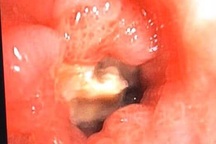

Sau khi được bác sĩ thăm khám và làm các xét nghiệm, cận lâm sàng, bệnh nhân được chẩn đoán bị dị vật tiêu hóa do xương cá cắm vào D2 tá tràng.

Các bác sĩ tiến hành can thiệp nội soi gắp dị vật.

Các bác sĩ đã gắp ra khỏi tá tràng người bệnh mảnh xương cá dài khoảng 0,3 x 6 cm an toàn. Bệnh nhân được chuyển xuống khoa Ngoại tổng hợp tiếp tục điều trị và theo dõi sức khỏe.